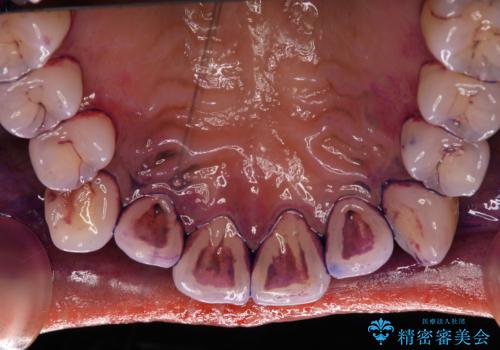

- 着色落としをして欲しいとのことで来院されました。

PMTC60分コースを行いました。

矯正中は汚れが付きやすいため、着色がとても多く付いていました。

抜歯したスペースや装置の周りの磨き方などとても難しため、定期的にクリーニングをおすすめします。